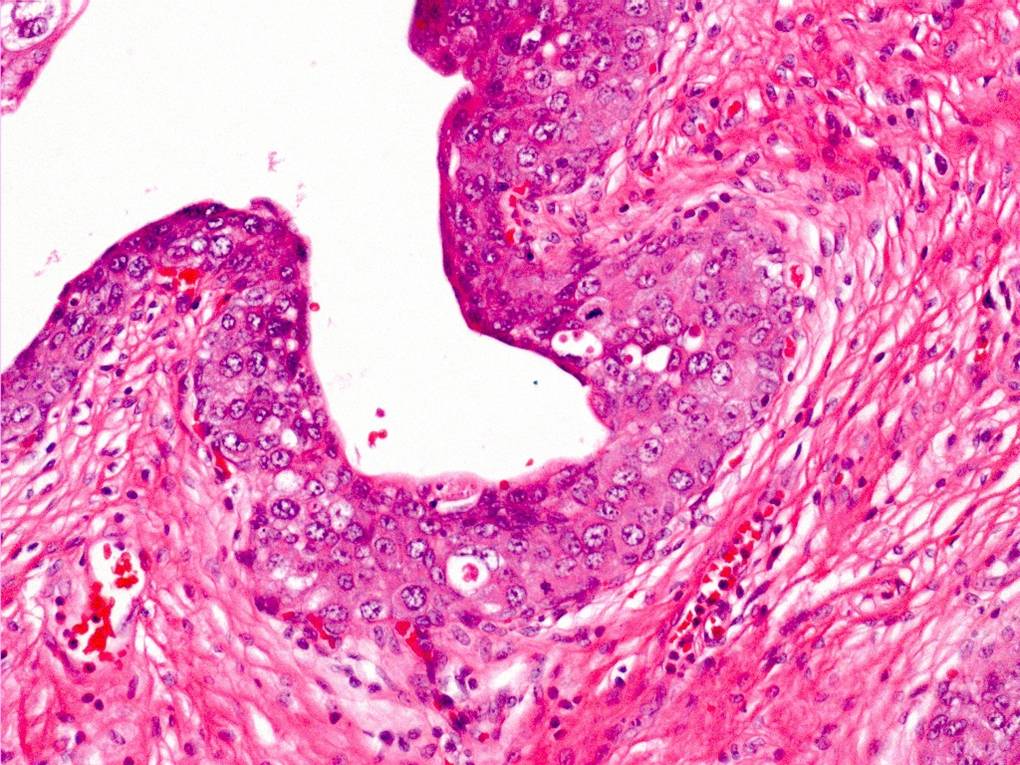

Bladder Flat Lesions

Case ID: 145